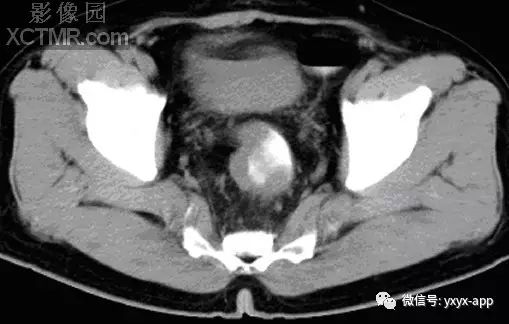

【影像表现】 钡灌肠:直肠与乙状结肠起始部可见不规则充盈缺损(图1箭头),肠管见偏心性狭窄;粘膜皱襞紊乱,纠集(图2、3箭头)。 CT:直肠壁不均匀增厚,见软组织影突入直肠腔内,增强扫描中度强化,周围脂肪间隙欠清楚,直肠后方可见肿大淋巴结(箭头)。肝脏体积增大,肝内密度欠均匀,可见多发弥漫不均匀低密度区,增强扫描病灶显示更加清楚,呈多发结节样低密度影,脾周及胆囊窝周围可见少量液性低密度影。

【诊断】 直肠癌

CT:(1)肠壁增厚,增厚的肠壁黏膜面多明显凹凸不平。(2)腔内肿块影,偏心性,呈分叶状或不规则形,与正常肠壁分界清楚,肿块表面可见小溃疡,呈火山口样。(3)肠腔狭窄,且为非对称性。(4)增强扫描可见较明显异常强化。(5)浆膜及临近器官受侵表现。